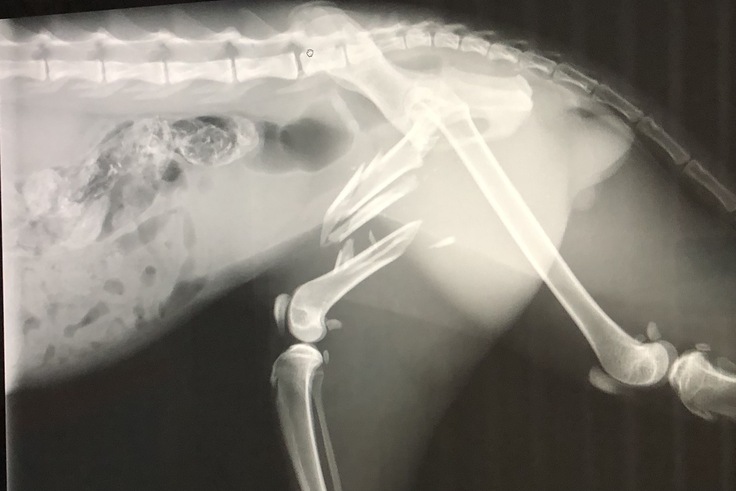

レントゲンで、左大腿骨が粉砕骨折しているとのこと。

骨が飛び出なかったのが奇跡というほどでした。

手術をして、プレートとボルトをいれること。

レントゲン検査、感染症検査完了

左大腿骨にボルトとプレートを入れる手術が完了

事故にあい左大腿骨を粉砕骨折。耳の付け根、口の周りを裂傷。

粉砕した骨をプレートとボルトで繋ぎ合わせる手術。